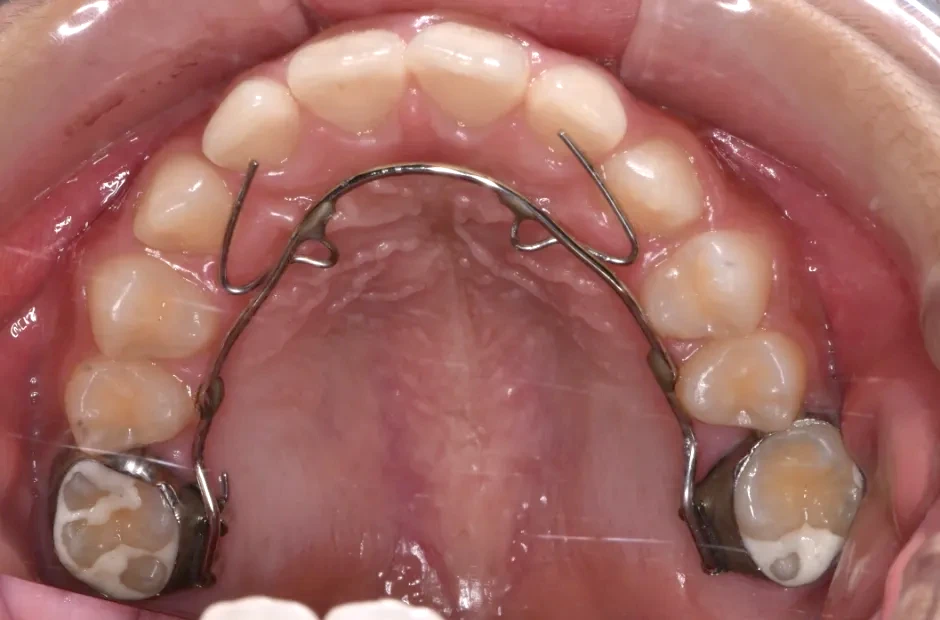

反対咬合

| 診断名・主訴 | 前歯反対咬合 |

|---|---|

| 年齢・性別 | 12歳・男性 |

| 治療期間・回数 | 1年半 18回 |

| 治療に用いた主な装置 | リンガルアーチ(前方誘導弾線) |

| 抜歯部位 | なし |

| 治療費 | 35万円(税抜) |

| リスク・副作用 | 装置による違和感・疼痛・歯肉退縮・歯根吸収・虫歯のリスクなど |